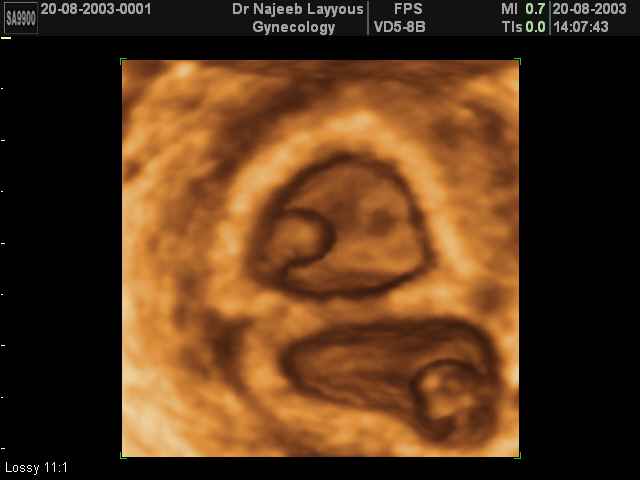

- 3D Photos échographie de grossesse multiple

3D Photos échographie de grossesse multiple : Jumeaux, triplés et quadruples| Dr N Layyous